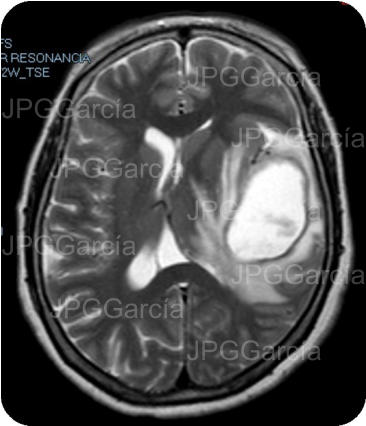

Resonancia magnética de cráneo en secuencias T1 y T2 que muestran una lesión ocupante de espacio de localización fronto temporal izquierda que ejerce efecto de masa aunado a edema perilesional